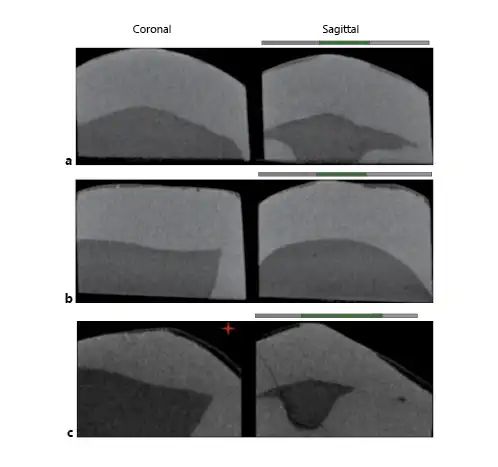

Samples were scanned by 3-dimensional X-ray micro-CT (Skyscan 1,172, Bruker MicroCT, Kontich, Belgium) along with a reference standard (1-mm thick aluminum wire of high purity >99.999%; Sigma-Aldrich, St. Louis, USA) and linear attenuation coefficient of 0.767326/cm. For image acquisition, a 4.88-μm pixel, 100-kV voltage (a peak emission energy of 59 keV; according to the manufacturer), a 100-μA amperage, 180°-rotation, 3-frame average, 0.5°-rotation pitch, and AlCu filter were used. The images were reconstructed and converted to bitmap by nRecon software v1.5.23 with 10-smoothing, 18-ring artifact reduction and 25% beam-hardening. The images were aligned with the DataViewer morphometric visualization software (Bruker MicroCT). One 2-dimensional (2D) image was extracted from each of the 3 studied locations of the specimen, i.e., the occlusal (500 μm from the occlusal side), cervical (500 μm from the cervical side), and middle thirds. From each 2D image, 2 areas (left and right to the internal control) were analyzed, totaling 6 areas analyzed per sample (Fig. 1, sagittal view). The left and right outcomes were averaged and considered for the statistical analysis. The presence of wear facets was determined using 2D images in DataViewer software (Bruker MicroCT). The facets had a flat appearance (Fig. 1c). The anatomical location and the side where the wear facet was observed were tabulated and used in the data analysis.

Fig. 1

Micro-CT images. a Sample with young dental age. b Sample with advanced dental age. c Sample with wear facet (red star). Coronal sections show only the decayed area of the samples. Sagittal sections: gray lines signal areas exposed to demineralization. The green line signals the central area of the block that has been protected (internal control). Left side shows the wear facet.

This study contributes to the limited literature on the effect of enamel age on caries susceptibility. Although conceptually ideal, designing a clinical study for this purpose would be challenging, due to the difficulty in obtaining enough dental samples of different ages for the specific laboratory analytical testing, within a reasonable amount of time. To overcome this limitation, we used already extracted and deidentified human premolars. The ages of the teeth were estimated by validated forensic methods, similar to the approach used in our previous study [Algarni et al., 2018]. The controlled conditions of this in vitro study allowed us to observe a significant decrease in the integrated mineral concentration loss and increase in the depth of the caries-like lesions, as functions of a tooth aging (Fig. 1a, b). This contrasts with the previous findings that indicated reduction in the artificial caries susceptibility in older enamel [Kotsanos and Darling, 1991]. Structural, chemical, and physical factors related to enamel can help clarify such differences.